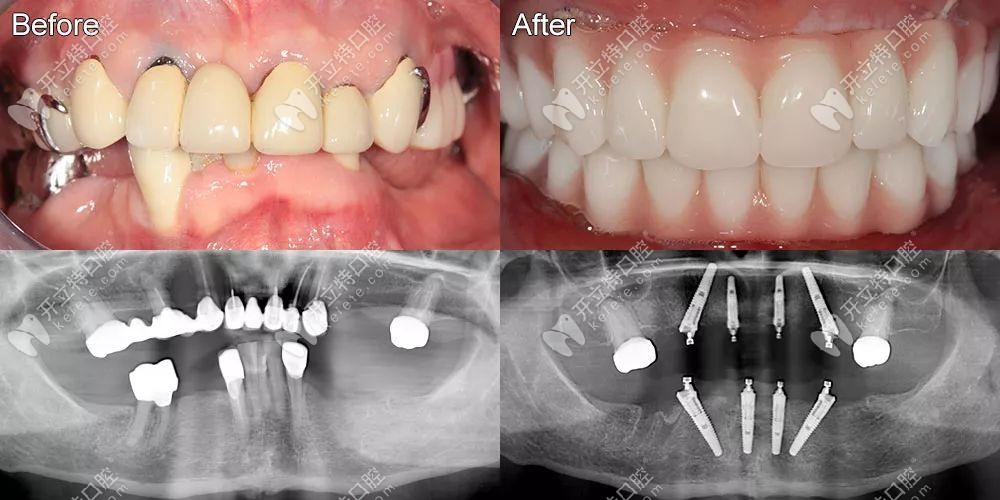

即刻負(fù)重4顆和6顆的真實區(qū)別已發(fā)放,它的優(yōu)勢是當(dāng)天戴牙冠

不少叔叔阿姨對即刻負(fù)重技術(shù)有了一定的了解,知道當(dāng)天種當(dāng)天就能戴牙冠吃東西,但是對于allon4和allon6的區(qū)別是一知半解的,想做的就快看看。